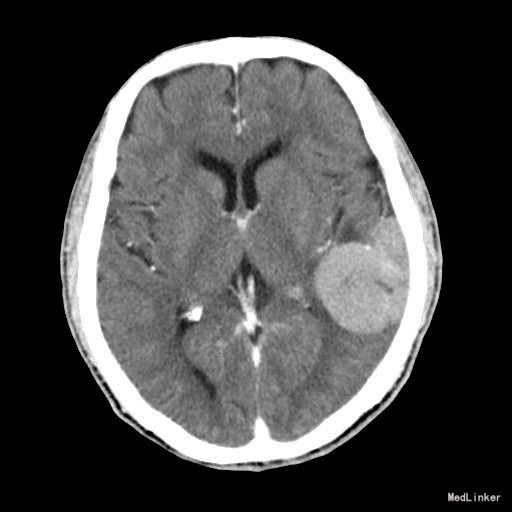

主诉:头晕、言语不清2月余 病史:老年男性,亚急性起病。患者2月余前无明显诱因出现头晕、言语不清,无头痛,遂至当地医院就诊,行头颅MR结果示:左颞部脑膜瘤。现患者为求进一步诊治来我院我科住院治疗。

查体:神志清楚,查体合作,理解力正常,言语不清、欠协调,视力视野未见异常,病理反射未引出,无脑膜刺激征。 辅查:左侧颞叶肿块,考虑肿瘤性病变,脑膜瘤可能性大。

诊断:脑膜瘤 治疗:行“左侧颞顶占位病变切除术”,术后恢复良好。

随访:术后病理追踪:(脑膜瘤)镜下见肿瘤由梭形细胞构成,部分细胞呈漩涡样排列,细胞有异型性,核分裂象罕见,结合免疫组化,可符合脑膜瘤(WHOⅠ级)。 讨论:脑膜瘤是颅内常见肿瘤之一,来源于硬膜内的蛛网膜绒毛细胞,绝大多数为良性,起病缓慢,病程长。影像上一般诊断不难,CT上表现为:肿瘤位于脑外,以宽基底与颅底或硬脑膜相连,平扫呈等或高密度,呈圆形或卵圆形,增强扫描均匀明显强化。